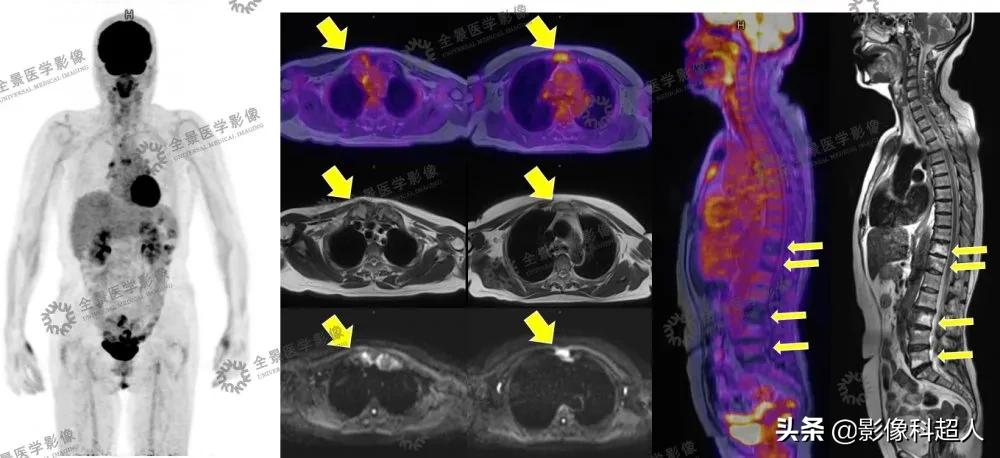

全景PET/MR影像资料

多模态影像可见: • 双侧锁骨头、胸骨柄骨质肥厚,密度不均匀增高,T2WI呈不均匀低信号,DWI呈不均匀高信号,右侧胸锁关节FDG轻度摄取增高,SUVmax=2.5• 胸骨体上段见局灶性FDG摄取增高,SUVmax=3.7,DWI呈高信号,ADCmin=1.401,余序列未见明确显示,骨质密度未见明显异常• T11、T12、L3、L5椎体骨质密度不均匀增高,前角为著,T2WI呈高信号,DWI呈高信号,ADCmin=0.679,FDG摄取缺失

根据刘女士的影像检查表现,医生进一步询问刘女士相关临床症状,刘女士表示并没有明显的皮肤改变。 经过全面观察分析、会诊讨论后,根据典型的胸肋锁骨区、椎体前角受累等骨质硬化改变,医生考虑患者为 SAPHO综合征可能性大。

影像学,尤其是系统性全身性影像评估在本病诊断中扮演重要角色。

- CT可用于评估骨质侵蚀、骨皮质肥厚、髓腔硬化等表现。

- 应用18F-FDG PET/MR所显示的18F-FDG摄取增高可以提示活动性炎症的存在,未见18F-FDG摄取增高的病变区可能提示非活动性或慢性炎症。结合MR显像能够敏感显示CT所不能显示的滑膜、韧带附着点炎症及CT所不能显示的轻微骨质病变,并可显示骨和软组织的水肿改变。 综合应用PET/MR显像可鉴别该病的活动性,并可评估全身累及情况,为临床治疗提供充分的影像学依据。